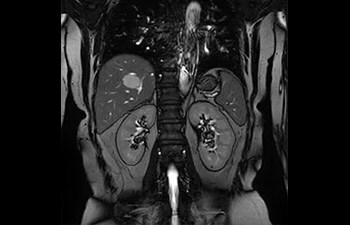

• Se puede usar con todos los contrastes y con todas las regiones anatomías.

con Compressed SENSE